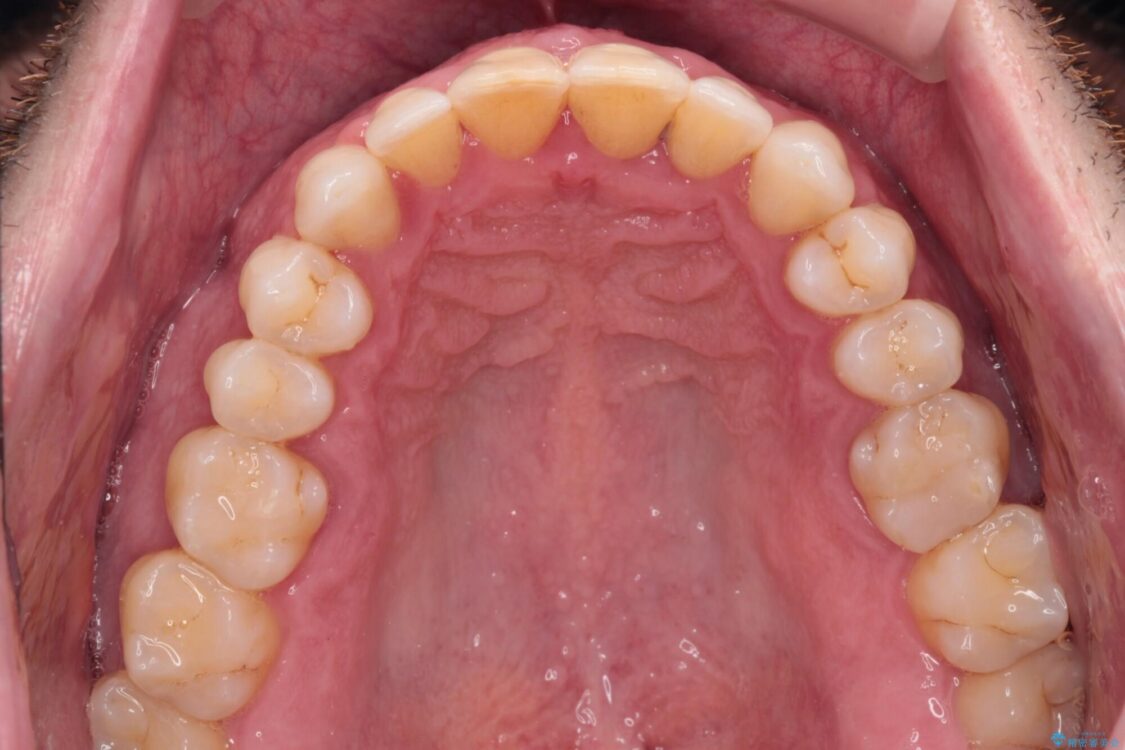

以前矯正治療を経験されたそうですが、舌の突出癖により上下前歯に隙間ができている様子でした。

治療前

• 前歯でものを噛みきりたい 目立たない装置でのワイヤー矯正 治療前画像